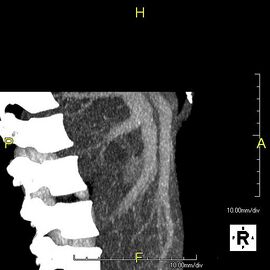

-

منظر جانبي بإسقاط الشدة القصوى لنفس المريض كما في الصورة السابقة.